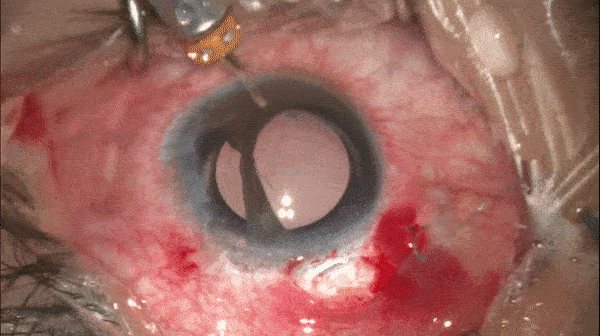

Step 13

离断虹膜间缝合

使用27G针头从颞上方角膜缘进针,分别穿过两端虹膜后从颞下方角膜缘穿出。

开睑器怎么用术说睛彩 | 金海鹰教授:使用8-0缝线的无巩膜瓣人工晶体固定手术_https://www.jmylbn.com_新闻资讯_第21张